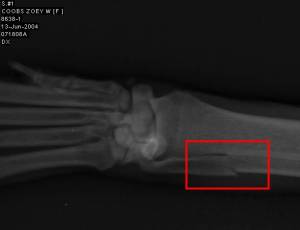

The next morning my mom returned Zoey to us (they were dog sitting). Unfortunately Zoey became the next victim of the Ulna curse. In one of her small dog syndrome fits she had attacked Molly, her aunt who happens to outweigh her almost 4 to 1. So our adventure began with a broken bone and ended with one.